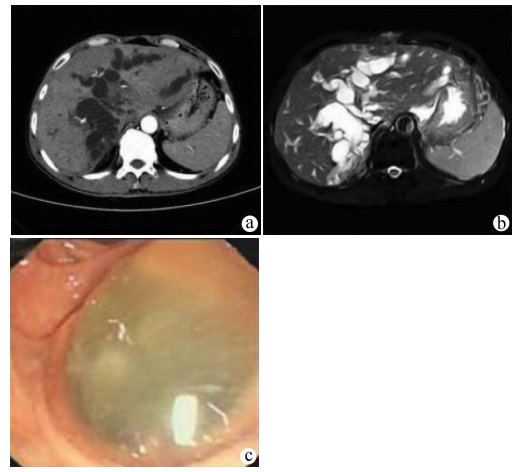

A case of primary carcinosarcoma of the liver

Wei YU, Chengbin ZHANG, Yan MA

2021, 37(12): 2890-2890. DOI: 10.3969/j.issn.1001-5256.2021.12.030

Abstract(760) HTML (212) PDF (3011KB)(72)

Abstract: